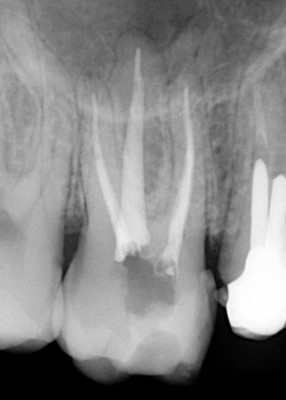

Podczas czynności związanych z leczeniem korzeni zębów endodonta – specjalista od leczenia kanałowego przy użyciu odpowiednich nowoczesnych narzędzi takich jak: mikroskop, lupy, maszynowe narzędzia rotacyjne czy ręczne narzędzia zwane pilnikami poznaje opracowuje i wypełnia techniką ciekłej gutaperki przygotowane wcześniej światło kanałów.

Wskazaniem po takiego leczenia są sytuacje, w których pojawiły się zmiany w okolicy wierzchołków korzeni lub podczas pierwszego leczenia kanałowego kanały zęba zostały opracowane i wypełnione w sposób nieprawidłowy – najczęściej nie zostały dopełnione do wierzchołka korzenia zęba. Obydwa przypadki można zdiagnozować na podstawie analizy obrazu radiologicznego.

Leczenie endodontyczne w Naszym Gabinecie odbywa się tylko i wyłącznie przy użyciu mikroskopu. Tylko odpowiednie powiększenie oraz doświadczenie lekarza pozwala na osiągnięcie odpowiedniego efektu ponownego leczenia kanałowego. Nasz specjalista Dr Mariusz Pietrzak wykonuje takie leczenie podczas jednego spotkania. Macie Państwo, zatem komfort nie tylko bezbolesnego leczenia, ponieważ zawsze odbywa się ono w znieczuleniu miejscowym, ale także kompleksowości ( na miejscu wykonujemy całą diagnostykę radiologiczną ) oraz sprawności leczenia, które można zakończyć podczas jednego spotkania.

Leczenie pod mikroskopem daje możliwości nie tylko uratowania zębów, których budowa anatomiczna nie pozwoliła wykonać pierwotnego leczenia poprawnie, ale także sytuacji, w których światło kanału zęba jest już niewidoczne i należy je odnaleźć oraz kiedy podczas próby leczenia zostało złamane narzędzie, którym lekarz próbował udrożnić kanał.

Udrożnienie kanału, w którym zostało złamane narzędzie pozwala wypełnić poprawnie kanały zęba i zachować go z dobrym rokowaniem na kolejne lata.

Usuwanie złamanych narzędzi w powiększeniu oraz opracowywanie trudnych anatomicznie kanałów zębów, które odbywa się pod mikroskopem i jest gwarancją, że leczenie będzie przeprowadzone poprawnie.